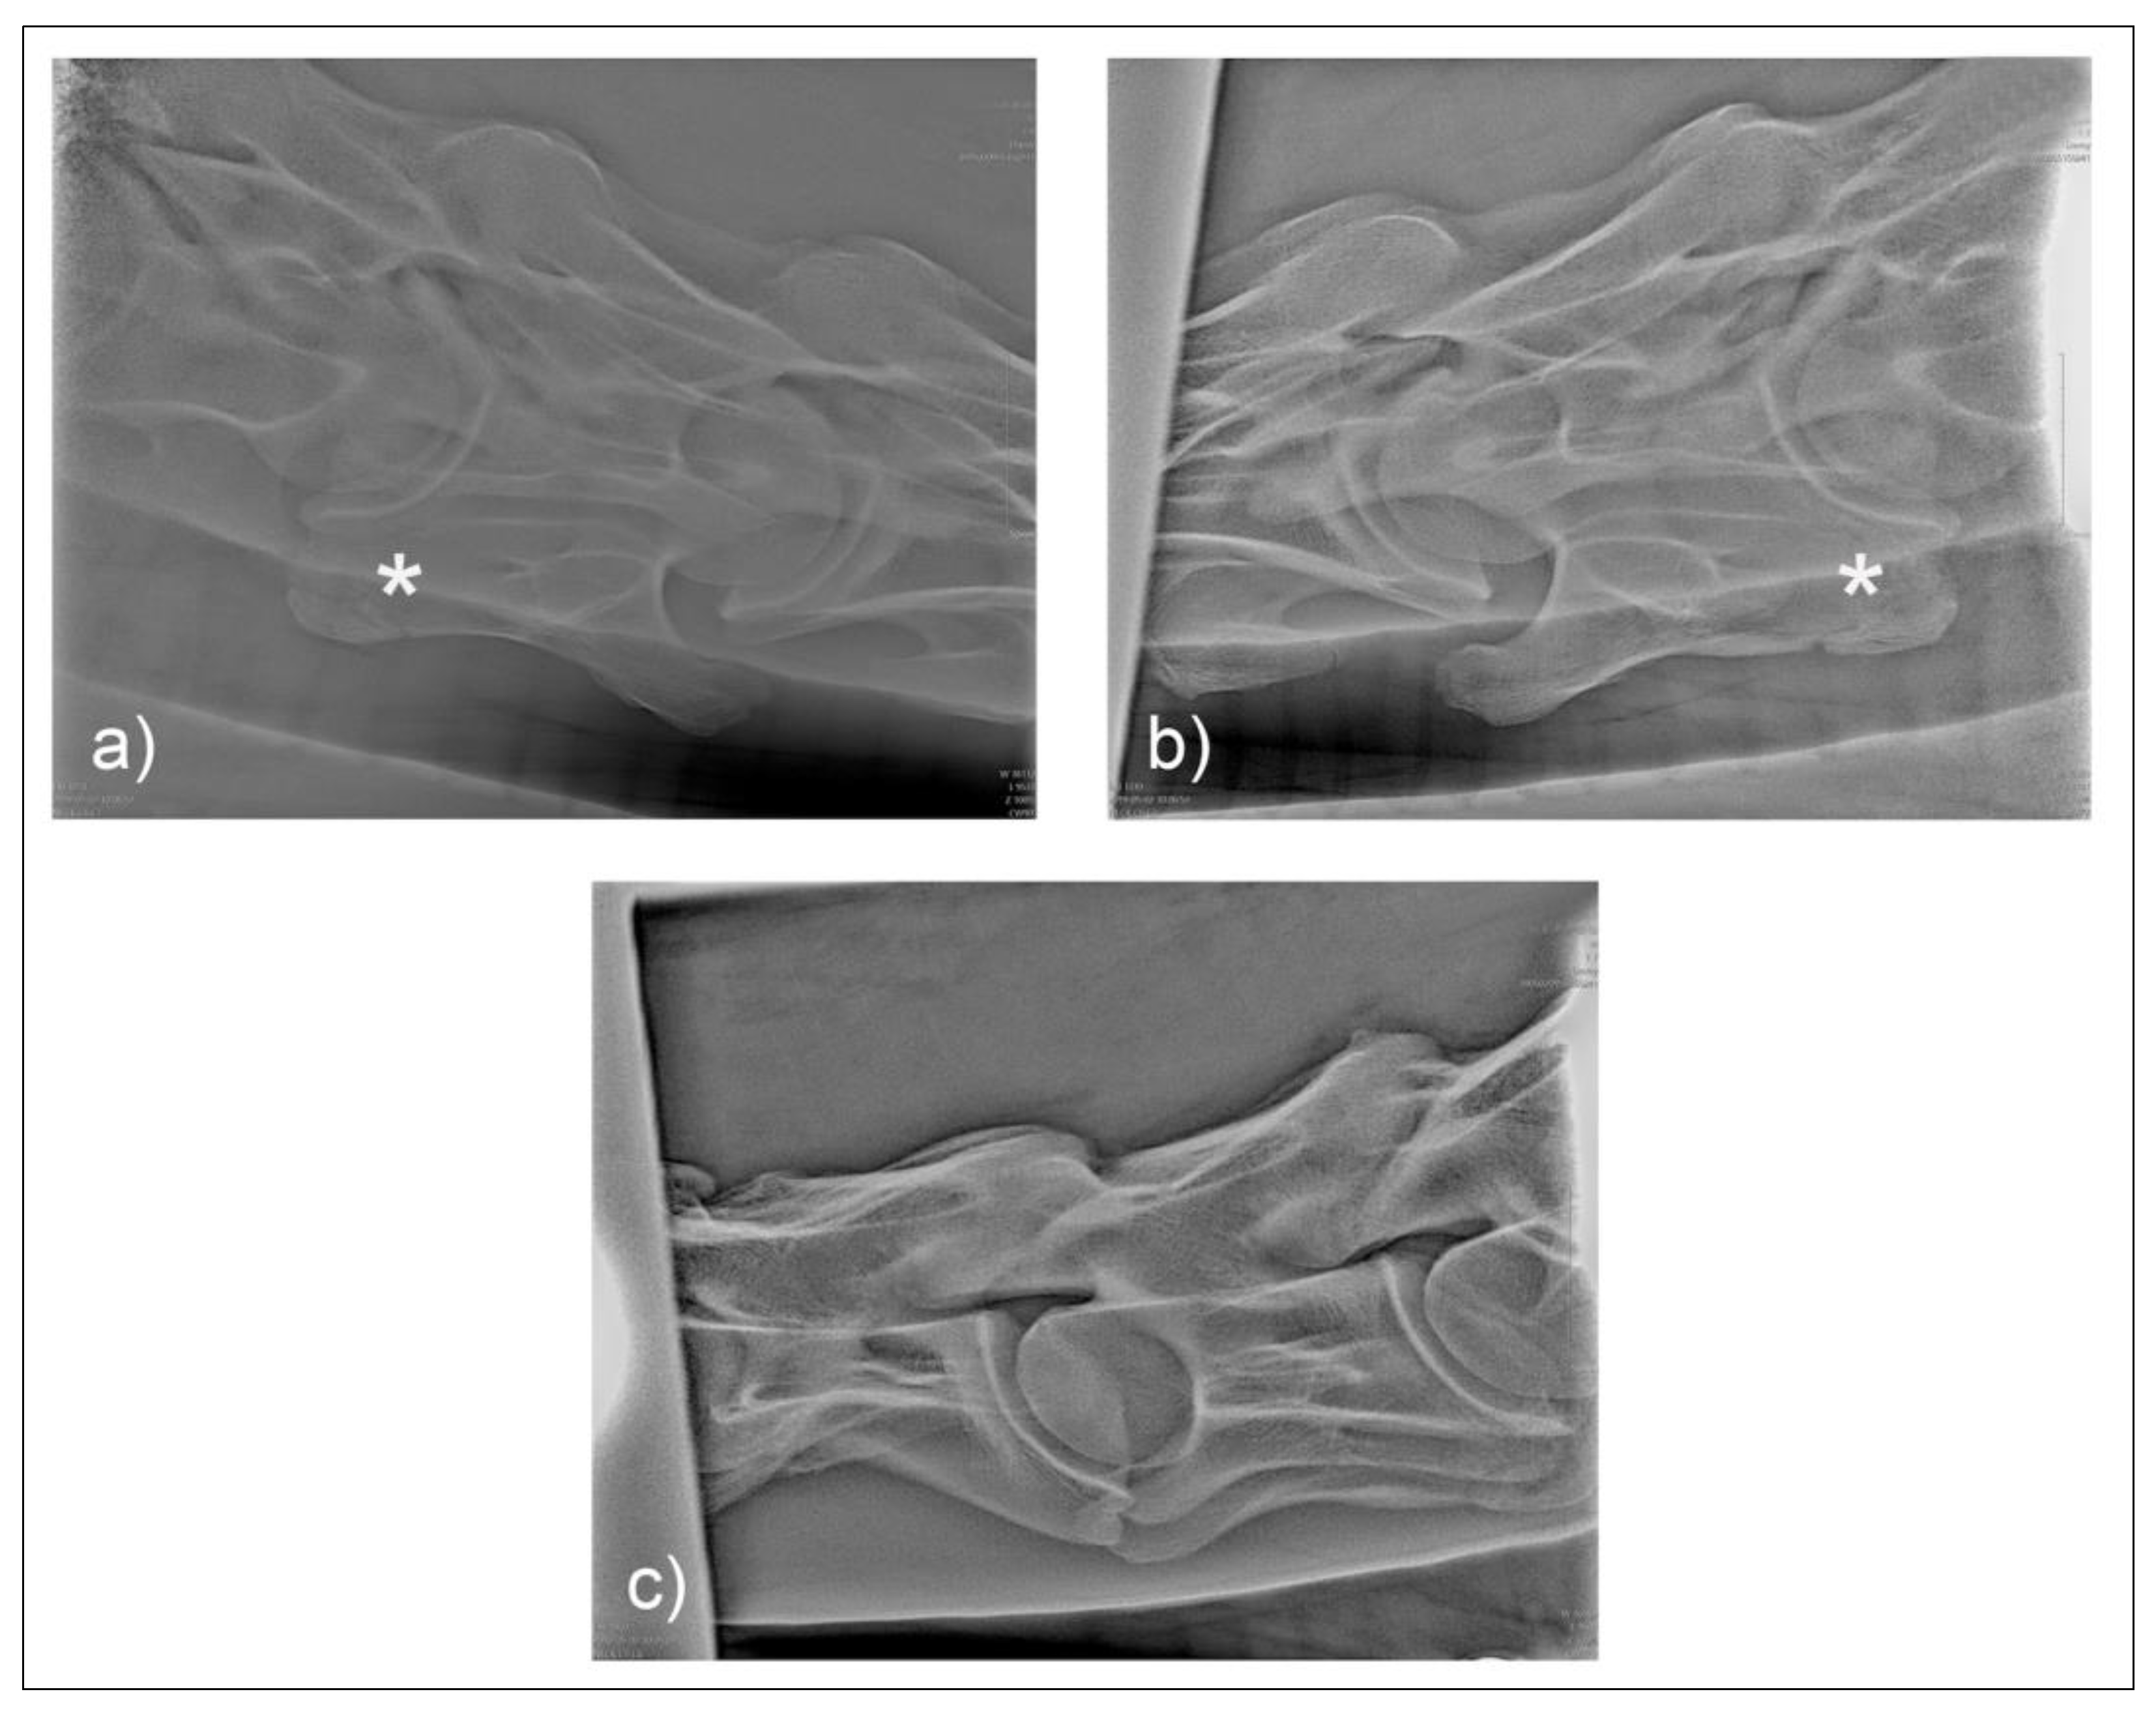

Figure 6. The ventral aspect of C6 (a) and cranial views of C6 (b) and C7 (c) of horse M1.

Figure 8. The ventral aspect of C6 (a) and cranial views of C6 (b) and C7 (c) of horse F1.

3. Results

On postmortem examination of horse M1, there was no gross transposition of the missing left caudal lamina on to the C7 vertebrae. There was, however, a small spur 2 mm from the ventral midline of the mid vertebral body on C7, which was otherwise symmetrical.

On postmortem examination of F1, the absent left caudal lamina of C6 was transposed onto the ventrolateral aspect of C7 creating a gross left to right asymmetry in C7 as well as the C6 vertebrae.

Two common operator and reviewer errors are identification of a false bilateral morphologic variation of C6 when actually imaging the normal C5 vertebrae. Conversely, diagnosing the bilaterally absent ventral laminae on C6 as normal is another common mistake (Figure 10c). It should be noted that the caudal ventral tubercles of C6 have separate centers of ossification that may be misdiagnosed as fractures [7]. Asymmetry of the articular process joints in the cervical spine may make true laterolateral image capture difficult [7]. The laterolateral images of C6, along with the dorsal to ventral oblique images, are key to interpreting the symmetry, length, and shape of the lamina (Figure 4c). Field radiographs make the assessment of transposition on to C7 difficult in some cases. The transposition may be visible less commonly on the oblique views (Figure 9b) depending on the shape and position of the transposition [11]. Transposition on to C7 is more commonly seen on the laterolateral views and is usually seen below the transverse processes [11]. In some cases, the transposition may be seen on the oblique view (Figure 9b). Some three-dimensional alterations are so severe that misinterpretation of the morphology on C7 can occur (Figure 8c). This highlights the need for more detailed diagnostic assessment in these cases. Spinal cord compression by an asymmetrical canal, articular process periarticular bone formation and extent of intravertebral foramina compression cannot be assessed by radiography alone [10]. The study of the prepared vertebra in three dimensions is key to understanding the potential alterations in regional biomechanics.

Withers [11] has also described a lateral 45°–55° ventral-dorsal left and right views. This was not utilized in this protocol, as the ventral lamina and caudal ventral tubercle of C6 was not highlighted against the trachea, which aids in visualizing the whole shape and length of the lamina. This view may, however, be useful if the dorsal oblique view is, for some reason, not possible or difficult to obtain. The left and right 30° dorsal to ventral views, in conjunction with the laterolateral views of C6 and C7, are necessary for a diagnosis or exclusion of ECCMV (Figure 4). The potential issues arising from these osseous malformations and their subsequent altered muscular attachments can be appreciated on the vertebrae in cranial and ventral views (Figure 6a–c and Figure 7a–c).